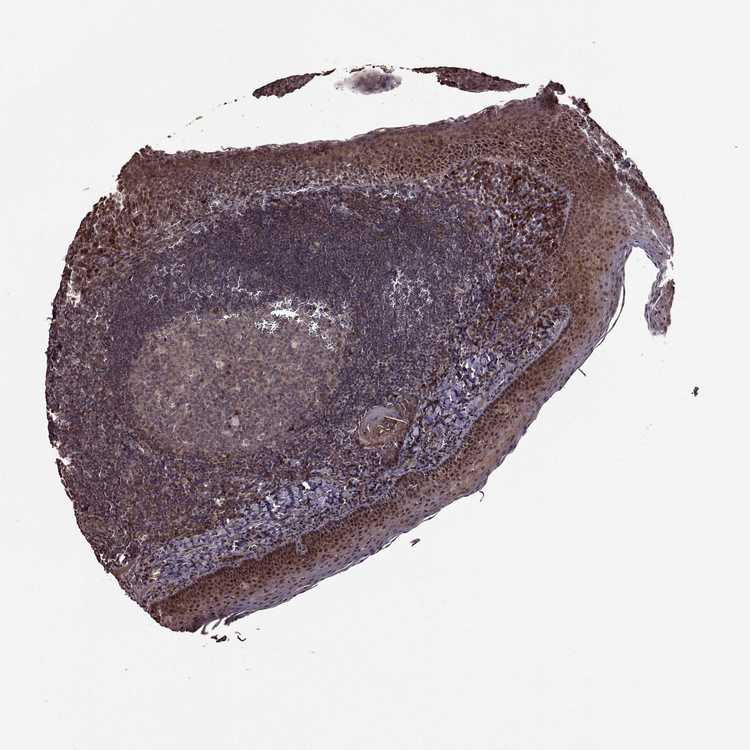

FBXW11